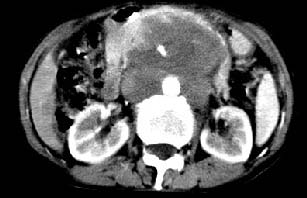

肝胃之间、胰头后、腹主a周围,融合而成团块状影,包绕血管,胰腺前移后缘分界欠清,与肝胃分界清,肿块未见明显强化,考虑淋巴瘤可能性大

胰腺受压前移,胰管扩张,应为腹膜后占位,病灶密度不均,有低密度坏死区,强化扫描强化不明显腹腔干动脉受侵,考虑腹膜后恶性占位

从发病部位(腹主动脉周围)及增强方式(均匀轻度强化、少量坏死)和病变形态(较大、多结节形)符合腹膜后淋巴瘤,建议颈部病变活检。

肝胃之间、肝十二指肠韧带,胰头后、腹主a周围,融合而成团块状影,包绕血管[腹腔干、肠系膜上动脉,腹主动脉],胰腺前移后缘分界欠清,与肝胃分界清,肿块未见明显强化,肝右叶后段小囊肿。

主动脉-胰腺间隙可见巨大分叶状软组织肿块影,包绕腹主动脉、腹腔干及其分支、腔静脉等大血管,增强呈无明显强化,临近脏器明显受压移位,增强示有分界。肝右叶可见局限性低密影,边缘清楚。

考虑腹膜后淋巴瘤。

影象诊断:考虑淋巴瘤待除外胃癌腹膜后淋巴结转移

讨论:首先看肠系膜和腹膜后的肿块我认为是多发融合的肿大的淋巴结。理由1大小不等的分叶,分布比较

自由。2其中的包绕的血管和周围少量的脂肪即所说的。

同时胃的影象表现和临床的不典型表现,所以我认为淋巴瘤,临床表现不支持胃癌